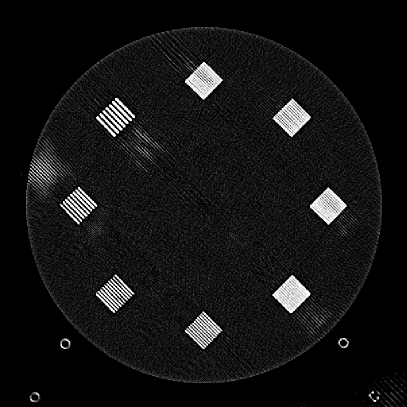

Figure 9: (a) The ACR phantom module 1 with 4 different inserts for CT number fidelity testing. In addition, two ramps of wires are visible near the phantom center. The image display window center is 150 HU and window width is 700 HU. (b) The phantom module 3 with a uniform water-equivalent radiodensity of 0 HU. The display window center is 0 HU and window width is 400 HU.

To evaluate image quality, we first tested the performance of JENG on a standard CT phantom, CT ACR 464 phantom 35. Then we tested JENG on 5 clinical thoracic datasets and 3 abdominal datasets. The ACR 464 phantom contains four modules in total, with each module 40 mm in depth and 200 mm in diameter. The first module has 4 different inserts to test CT number fidelity. In addition, the module contains a series of wires for cross-plane resolution evaluation, shown as white horizontal bars near the center in Fig. 9(a), and are visible in 0.5 mm z-axis increments. The second module tests low contrast resolution, but is not used in this paper. The third module, shown in Fig. 9(b), is a uniform cylinder of water-equivalent material of 0 Hounsfield units (HU), and we used this module to quantitatively measure image noise profile and in-plane resolution. The fourth module consists of resolution bars of various spatial frequencies for analysis on high contrast resolution. To scan the phantom, the scanner setup used dual sources with 2 focal spots at each source. In addition, the projections were acquired using the same protocol for clinical thoracic scans with 100 KV, a nominal tube current of 718 mA and a high helical pitch of 2.8. For all experiments, we compared JENG against the state-of-the-art Siemens ADMIRE, reconstructed with a BL-64 soft tissue sharp kernel, and we define ADMIRE as the clinical standard hybrid IR method for the rest of the paper.

The resolution bar visual comparison study, however, can be biased by observer subjectivity and may provide little information for spatial resolution beyond a limiting value. Therefore, we also quantitatively evaluated the Task-Based Modulation Transfer Function (MTFtask) of JENG and the clinical standard hybrid IR for a more complete analysis on in-plane resolution, using the edge of the uniform water-equivalent material phantom in module 3 as shown in Fig. 9(b). In summary, our MTFtask analysis was measured with the water-equivalent phantom and averaged all transaxial images in module 3 into a 2D image. Then the MTFtask analysis computed the oversampled edge-spread-function for the generated 2D image, differentiated and Fourier transformed the edge-spread-function to the frequency domain 38, 3. The MTFtask is then the absolute value of the Fourier Transform result and the source code of our MTFtask computations can be downloaded from citation 39.